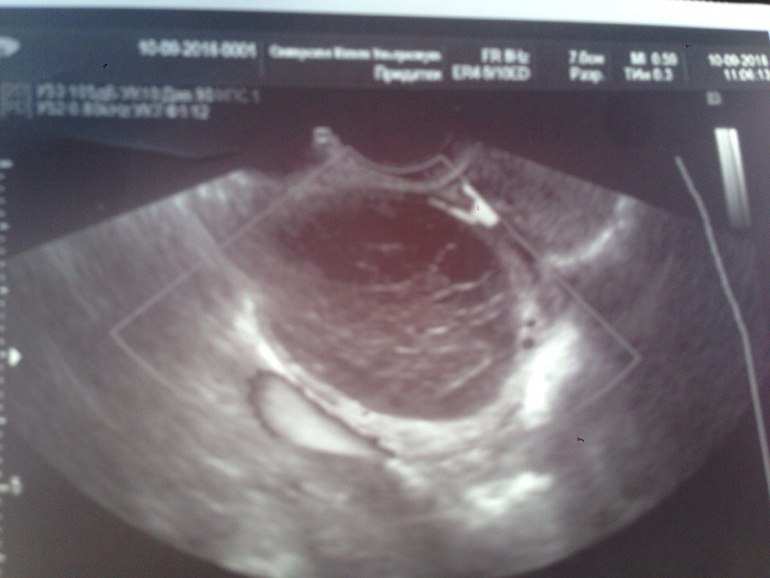

При глубоком эндометриозе яичников образуются заполненные темной жидкостью полости, которые могут различаться по размеру, известные как эндометриомы или «шоколадные кисты». Диагноз эндометриомы можно заподозрить на основании ультразвукового исследования таза, но окончательный диагноз должен быть основан на микроскопическом исследовании самой кисты.(см. ниже).

Когда дело доходит до визуализации, этим пациентам обычно назначают трансвагинальное ультразвуковое исследование, чтобы определить, есть ли причина боли в области таза, которую можно визуализировать.Поверхностные имплантаты эндометриоза нельзя увидеть ни на УЗИ, ни на каком-либо другом методе визуализации. Однако эндометриомы часто обнаруживают на УЗИ. Эндометриомы обычно выглядят как простые кисты. Однако их также можно рассматривать как множественные кисты или кистозно-солидные образования. Типичный вид этих поражений на УЗИ демонстрирует низкоуровневые однородные эхо-сигналы, иначе описываемые как внешний вид матового стекла. Это согласуется со старым геморрагическим мусором. Эти поражения также обычно лишены какой-либо васкулярности при исследовании с использованием допплеровского потока.[35] [36]